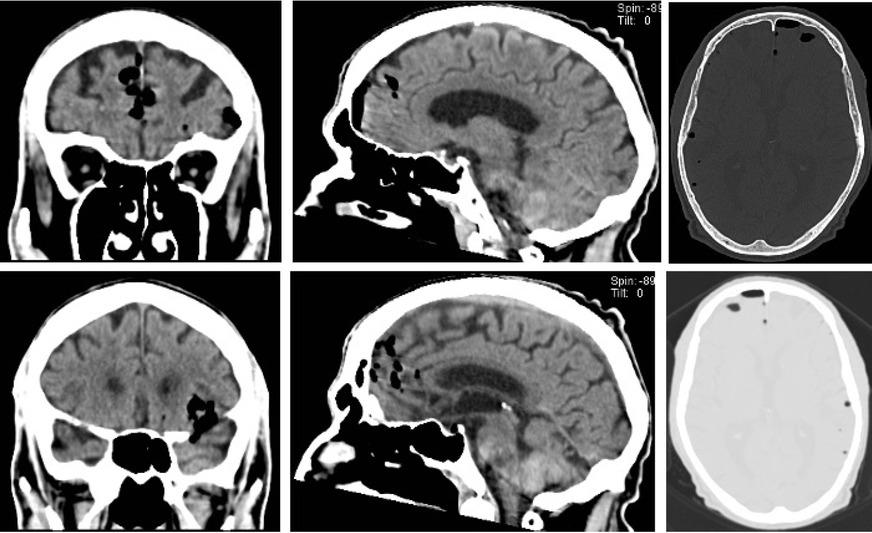

Due to the previous unintended dural puncture, a head CT scan was immediately performed. This showed multiple extra-axial air bubbles involving both hemispheres’ frontal and temporal lobes. (Figure 1).

Cranioencephalic computerized tomography after the surgery: the presence of several small gas foci scattered in an extra-axial location involving the frontal and temporal region of both hemispheres (with a slight left predominance).